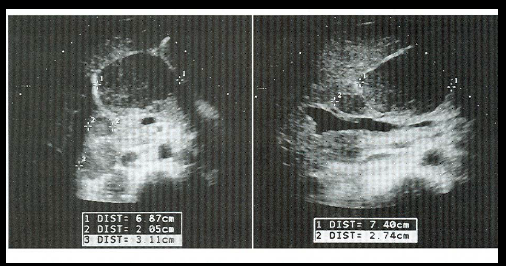

When lymph nodes are enlarged they cause a _____ to become evident. this is when an organ is being pushed upon by some type of mass lesion.

“mass effect”

what do you see int he top lt image?

mass effect

what are these examples of?

retroperitoneal lymph nodes